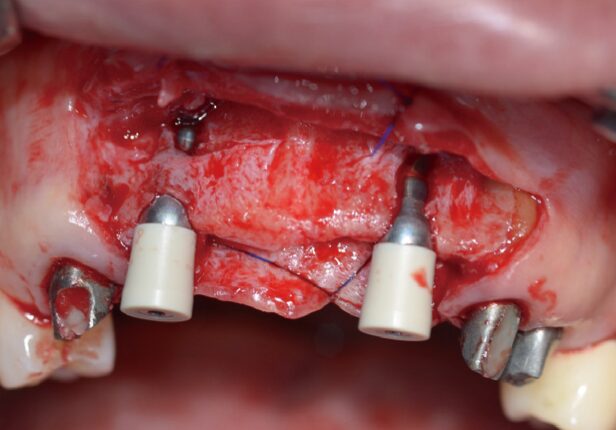

Implant placement

AXA positioning